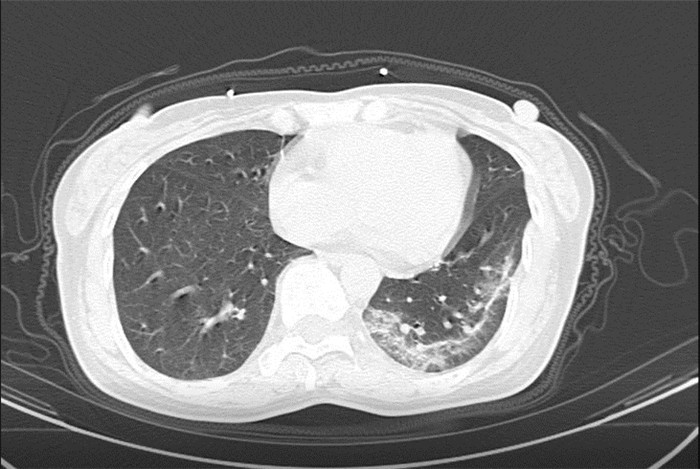

武漢大學(xué)中南醫(yī)院影像科副主任張笑春教授發(fā)現(xiàn),目前武漢市家庭聚集性發(fā)病較多,而且大多起病隱匿,一次甚至多次核酸陰性,無(wú)任何臨床癥狀,CT檢查卻已顯示為病毒性肺炎特征。

為了盡快篩查新型冠狀病毒肺炎患者,醫(yī)院會(huì)選擇影像診斷作為早期發(fā)現(xiàn)新型冠狀病毒感染的肺炎的重要一環(huán)。

CT為當(dāng)前首選篩查與診斷的主要影像學(xué)手段,胸部CT的病毒性肺炎檢出率高。

方舟CT(CT Ark)可以滿(mǎn)足全面的臨床功能,配置16層、32層、64層、128層CT,實(shí)現(xiàn)了低劑量掃描要求,配合NDI微劑量迭代技術(shù),智能毫安調(diào)控技術(shù),使各種場(chǎng)合下、各部位低劑量掃描得以實(shí)現(xiàn);超高分辨率CT病灶靶掃描,使病灶的密度顯示更加精確,能夠顯示病灶內(nèi)輕度的密度變化,有利于小病灶的密度定量分析和及時(shí)診斷。